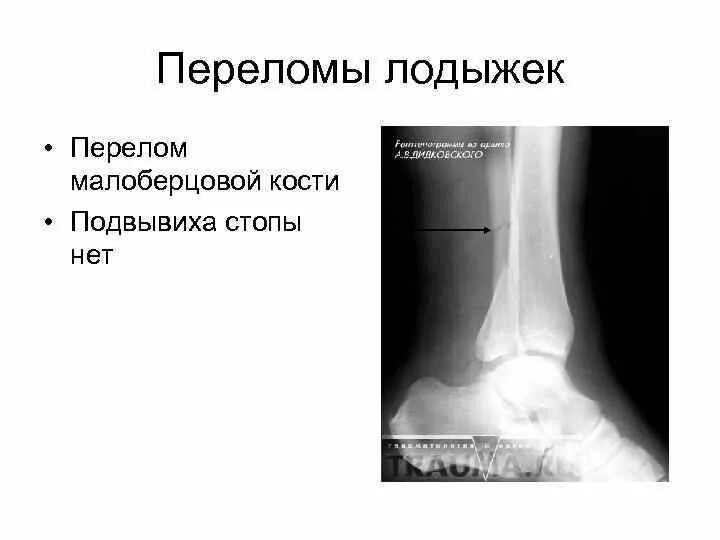

Перелом дефект